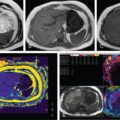

PC is a minimally invasive procedure which involves placement of a drainage catheter into the gallbladder, usually under USG guidance. It is most commonly performed to decompress an inflamed gallbladder in cases where surgery is not possible due to associated comorbidities. The indications of PC can be divided into those that require access into the gallbladder and those that require biliary tract access. The common indication for PC is acute cholecystitis due to calculus obstruction of the gallbladder neck or cystic duct in poor surgical candidates or patients with severe cholangitis. The definitive treatment for acute cholecystitis is laparoscopic cholecystectomy. Another application is for stone removal or percutaneous cholecystolithotomy through this route. PC can also be used for biliary drainage or decompression in cases where the biliary system is not dilated, particularly when the obstruction is below the level of cystic duct–bile duct junction. PC is also used for biliary diversion in the setting of a bile leak or duodenal fistula in inflammatory or traumatic conditions, thereby reducing the risk of biliary peritonitis. For intraluminal procedures, PC can act as an access portal in case the peripheral bile ducts are inaccessible. The prerequisite for PC is that the gallbladder must be distended for allowing its puncture. Contraindications to PC include unavoidable interposed bowel segment between the gallbladder and the puncture site and biliary peritonitis. Presence of coagulation disorders is a relative contraindication. This includes review of the patient’s clinical status and imaging. Screening USG should be done to evaluate the gallbladder – whether distended or not, the site of obstruction, and to decide the approach. PC is usually performed under real-time USG guidance. CT or fluoroscopic guidance is rarely used due to limited availability, exposure to ionizing radiation and higher cost. In sick patients, the procedure might need to be performed at the bedside, making USG a suitable modality. Like other invasive procedures, the blood parameters need to be evaluated (PT/INR, platelet count, renal function tests). An informed consent should be obtained. Intravenous access should be established. Patients who are candidates for cholecystostomy are usually sick and are usually on antibiotic treatment. In case where it is not so and there is clinical evidence of infection, third-generation cephalosporins and macrolides for covering anaerobic bacteria may be administered. This procedure is mostly done under USG guidance as this technique is readily available for bedside and emergency procedures and more cost-effective. It can also be performed under CT or fluoroscopy guidance. The procedure is done under local anaesthesia. The patient lies supine or in the left lateral position and the area is cleaned and draped. Based on the position of the gallbladder, a preferable access route is chosen, either transhepatic or transperitoneal. The second decision is about the puncture technique, which may be modified Seldinger or trocar. An 8F catheter is usually placed to allow drainage of bile. If the bile is thick and infected, a 10F or 12F catheter may be necessary. Locking pigtail catheters are useful in reducing the incidence of catheter dislodgement. The two USG-guided approaches used for PC are transhepatic and transperitoneal, of which the former is usually preferred. In the transhepatic approach (Fig. 9.24.14), the gallbladder is punctured through the liver parenchyma, generally the bare area. The traversed liver parenchyma provides better support for the catheter and helps in reducing the incidence of bile leak into the peritoneal cavity and thus biliary peritonitis. However, since liver is a vascular organ, there is an increased risk of bleeding due to the puncture of the liver. Thus, this approach should be cautiously used in patients with liver dysfunction and coagulopathies.